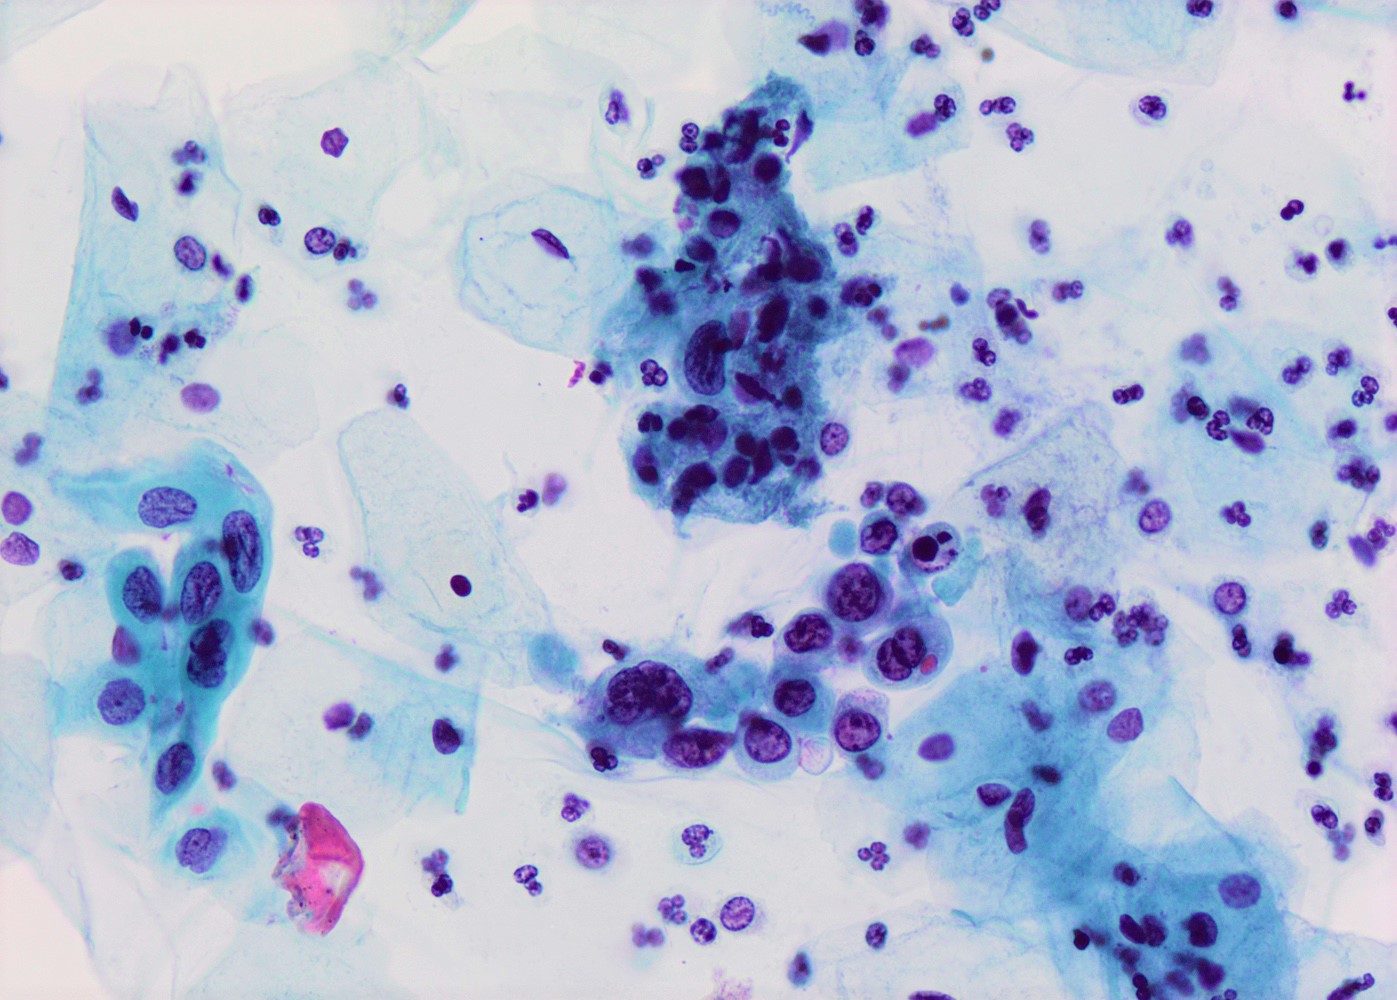

- High nuclear to cytoplasmic (N/C) ratio, nuclear enlargement (usually threefold), hyperchromasia, coarse chromatin, nuclear membrane irregularities and inconspicuous nucleoli

- Arranged as syncytium / hyperchromatic crowded groups or single cells

- Additional information available at: HSIL cytology

- References: Nucci: Gynecologic Pathology - A Volume in Foundations in Diagnostic Pathology Series, 2nd Edition, 2020

Cytology images